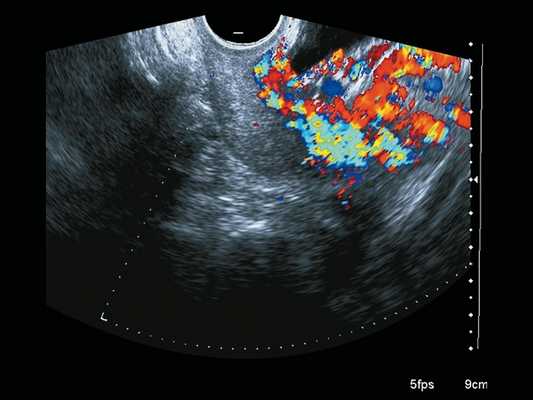

Сканирование в сроке 32 +4 нед беременности проводилось на ультразвуковом сканере премиум-класса W10 (компании Samsung) c использованием конвексного (CA1-7A) и внутриполостного (EV3-10B) датчиков с применением технологии LumiFlow™ (рис. 4-7).

Рис. 7. Беременность 32 +4 нед. Режим LumiFlow™: сосудистые мостики (rail sign) из миометрия сквозь серозный покров в стенку мочевого пузыря (стрелки).

В режиме серошкального сканирования все ранее идентифицированные особенности плацентации (PAS 3a): ретроплацентарные лакуны, васкулярная инвазия в шейку матки, исчезновение нормальной гипоэхогенной ретроплацентарной зоны, истончение миометрия, выпячивание плаценты, гиперваскуляризация пузырно-маточной зоны были подтверждены.

Дополнительное использование технологии стереоскопической визуализации кровотока (LumiFlow™) позволило визуализировать вовлеченность стенки мочевого пузыря беременной в конгломерат тканей аномальной плацентации (сосудистые мостики (rail sign) из миометрия сквозь серозный покров в стенку мочевого пузыря), то есть идентифицировать placenta percreta (PAS 3b). Проведенная в последующем МРТ констатировала полное предлежание плаценты с прорастанием в рубец, через все слои миометрия, шейку матки и цервикальный канал (рис. 8) и верхнюю стенку мочевого пузыря.

Таким образом, мнение E. Jauniaux и соавт., высказанное 6 лет назад [7], об отсутствии ультразвуковых признаков или их комбинации, специфичных для определения глубины инвазии плаценты, с внедрением в повседневную практику современных ультразвуковых технологий, LumiFlow™ в частности, может быть пересмотрено. Стереоскопическая визуализация кровотока, помогающая интуитивному пониманию структуры кровотока в мелких сосудах, является реальным инструментом в оценке степеней аномальной инвазии плаценты.